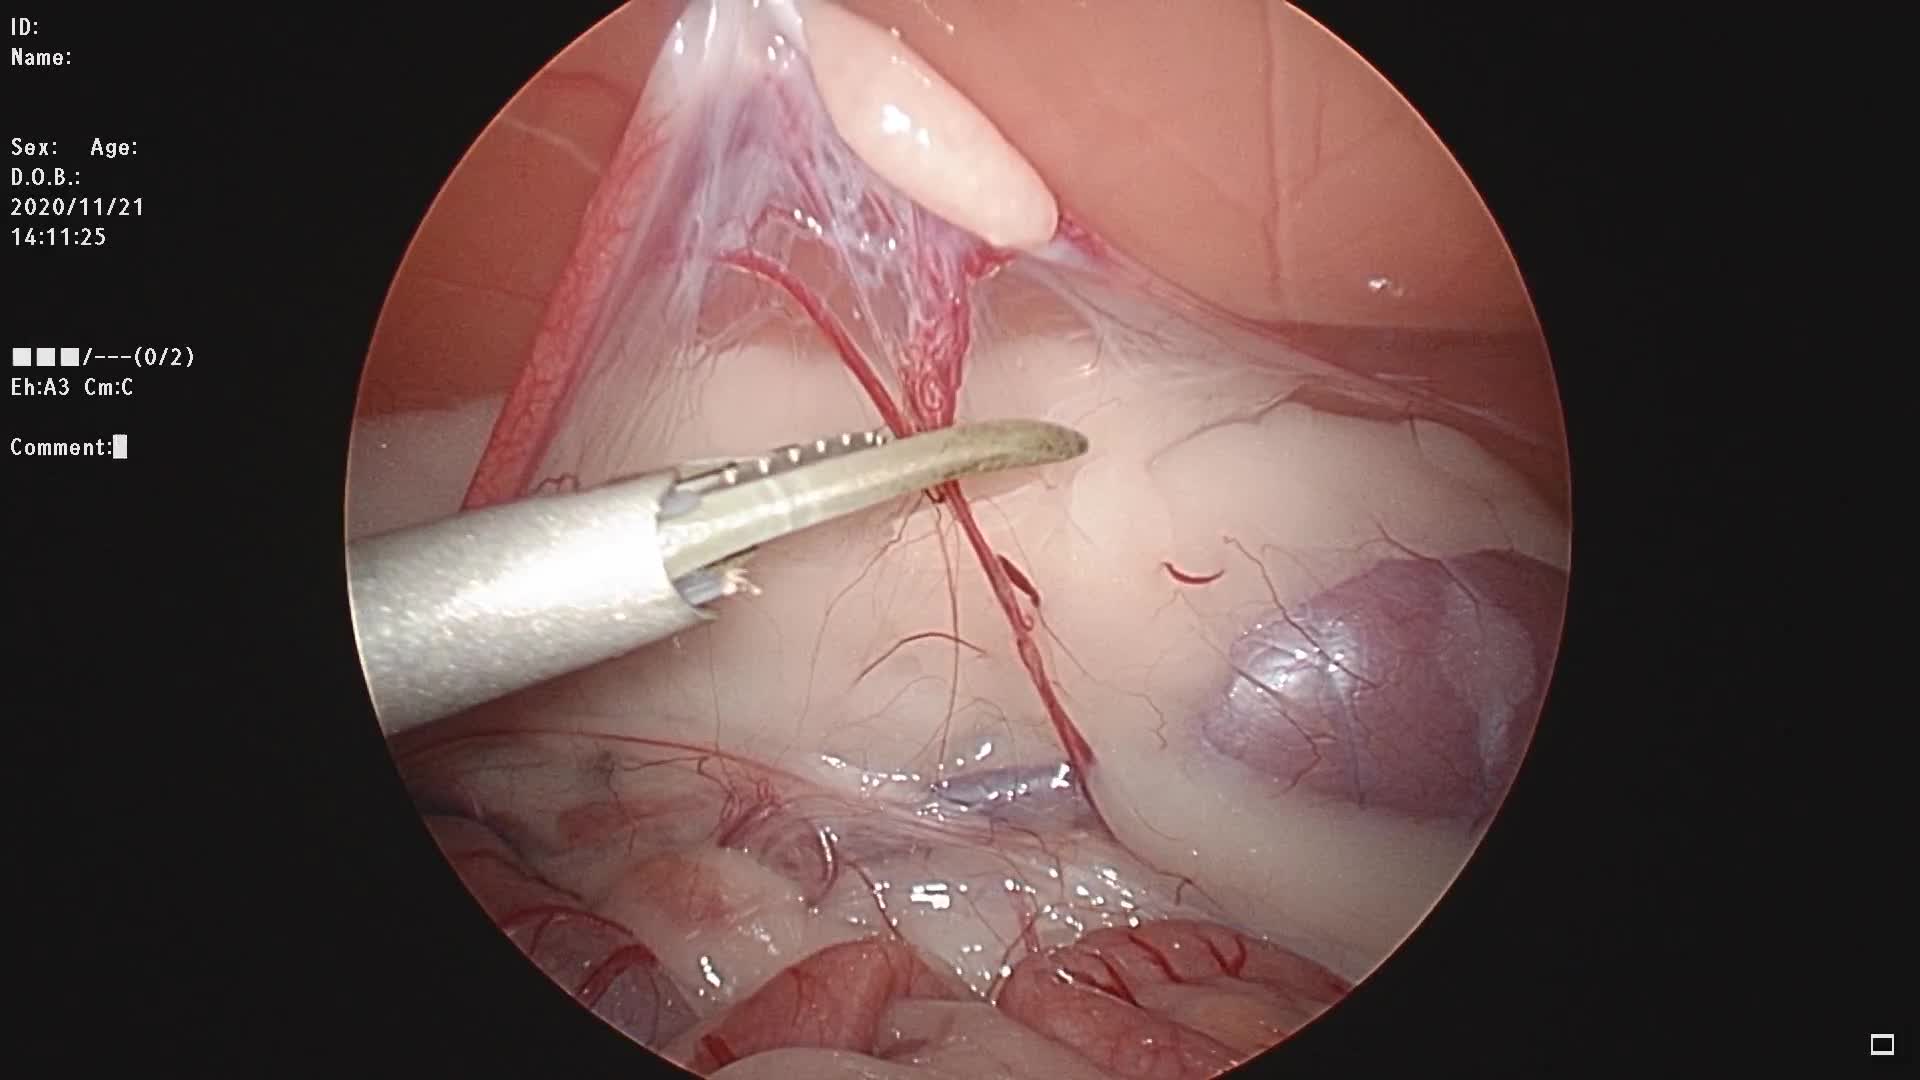

こちらは避妊手術の様子です。

腹腔鏡(ラパロ)とは、体表の皮膚から腹腔内に挿入する内視鏡の器具のことで、この内視鏡器具を使って行う手術を腹腔鏡手術といいます。腹腔鏡手術では、約1㎝のポートと呼ばれる穴を3カ所開け、1ヵ所は内部を観察するため内視鏡カメラを挿入し、残り2ヵ所に鉗子や電気メスを挿入して腹腔内で操作をしながら手術を行います。猫の避妊などでは2ヵ所の穴で行うことも可能です。